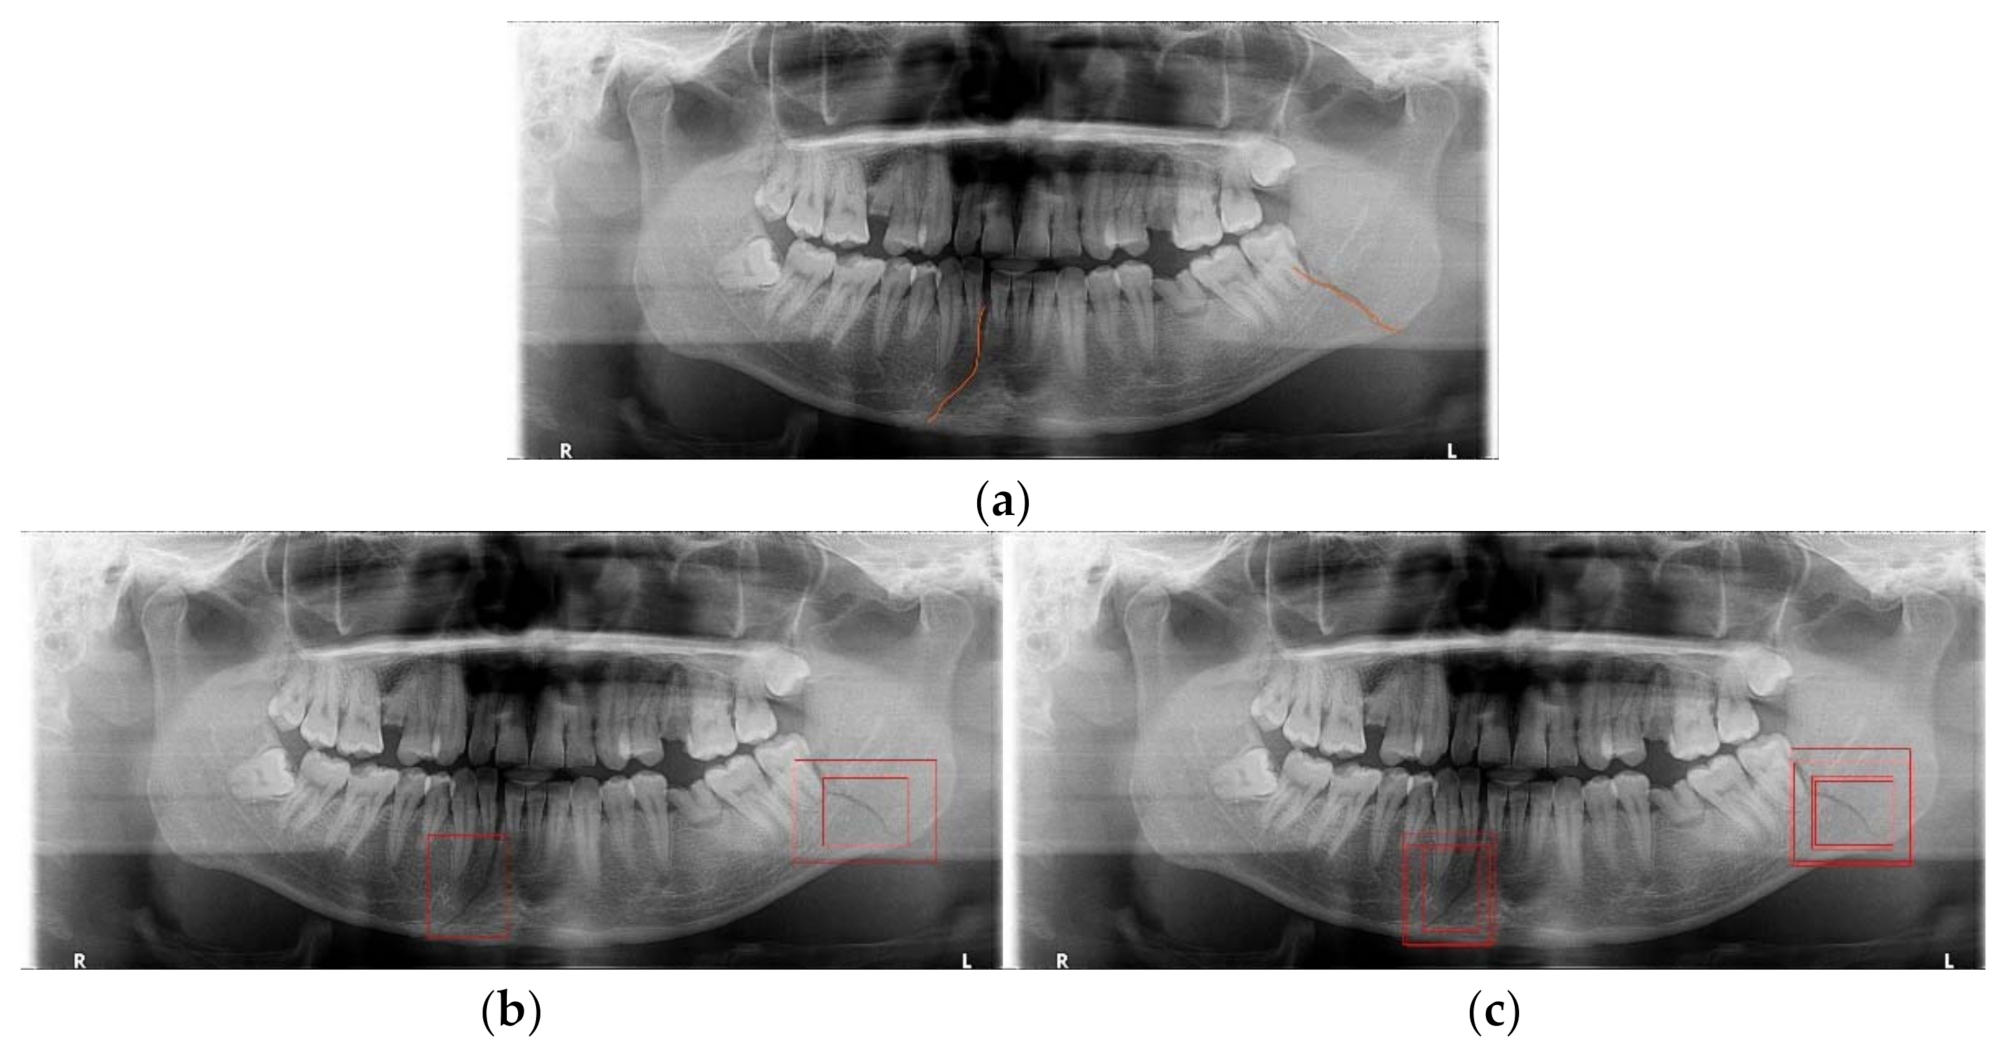

3.2. Detection Results